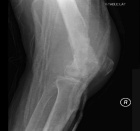

59 year old female complains of knee pain for two months

ESR 112mm/hr

CRP 156 mg/l

WBC 14.6

Zoom image: Radiological image Radiological image.